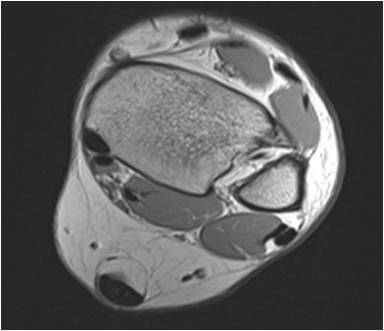

Gallery of Unlabled Radiographs from Lecture (Dr. French) - 2020

Click a thumbnail to enter the gallery display. Click the file name link at the bottom left of the gallery display to view the image at high resolution.